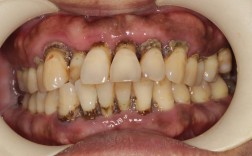

- 牙齿松动加剧: 牙周炎已经导致牙槽骨吸收、牙齿支持组织减少,矫正施加的力会进一步增加牙齿的松动度,甚至可能导致牙齿脱落或无法移动到目标位置。

- 牙龈退缩加重: 矫正过程中牙齿移动的方向和方式,如果牙周炎未控制,可能加速牙龈退缩,导致牙根暴露、牙齿敏感、美观受损。

- 骨支持不足: 牙槽骨吸收意味着牙齿移动的“土壤”不够坚实,牙齿移动可能不稳定、效果难以维持,容易复发。

- 牙周炎是牙齿矫正的“红灯”,未控制的牙周炎是牙齿矫正的绝对禁忌症。

- 成功矫正的关键前提是健康的牙周组织,必须在牙周炎症得到有效控制、稳定后,才能开始矫正。